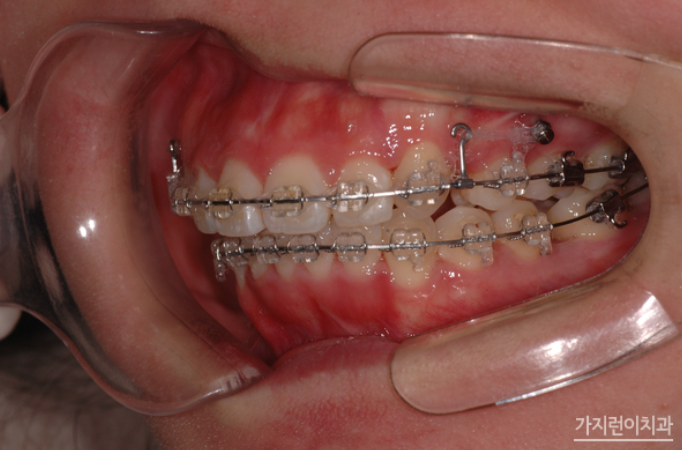

위 환자의 경우 상악 돌출입 증상과 더불어 심한 충치로 인해 발치가 불가피한 악조건을 갖고 있었는데요. 충치는 정도가 심하면 결국 발치를 하게 되고 인공치아를 식립해야 하는 과정을 밟게 되는데요. 그런데 환자의 경우 불규칙적인 치열의 재배열과 더불어 콤플렉스로 자리잡은 돌출입도 교정으로 진행해볼 수 있었습니다. Modified Bonded Cantilever Spring (MBC spring) 교정으로 사랑니에 직접 부착해 사랑니를 세우는 교정을 진행하게 되었는데요. 사랑니가 쓰러져 있는 상태라면 기존의 교정장치를 부착하기 어렵기 때문에 개발된 장치를 사용하고 있습니다. 그러면 장치를 착용한 후의 경과를 볼까요?

하지만 사랑니를 세우는 교정이라고 해서 모든 사람이 Modified Bonded Cantilever Spring (MBC spring) 교정을 사용하지는 않는데요. 환자분의 경우 하악 어금니 발치 공간을 메우는 과정에서 사랑니가 쓰러져 있긴 했지만 교정장치를 부착할 수 있는 상황이었기 때문에 추가적으로 Modified Bonded Cantilever Spring (MBC spring)을 사용하지는 않았습니다. 대신 돌출입 해결을 위해 상악을 후방으로 이동하기 위해 교정용 스크류를 이용해 진행하게 되었는데요. 총 2년 3개월의 치료기간이 소요된 환자분의 교정전후 사진을 확인해볼까요?

송곳니의 덧니 증상과 더불어 돌출입, 비뚠 치아배열 등 여러 문제가 많은 구강이었는데 어떤가요? 덧니의 흔적을 찾기 어려울 정도로 가지런하게 개선된 것을 확인할 수 있었는데요. 상악의 돌출감도 해소되었고 어금니 3개를 발치하게 되었는데도 티가 나지 않는 다는 걸 확인할 수 있었습니다. 그만큼 사랑니가 감쪽같이 어금니의 외형과 역할을 대신하게 된 것인데요. 충치로 치아를 발치해야 한다면 임플란트만 고집하지 마시고 본인의 구강상태에 따라 사랑니를 바로 세워 치아교정으로 임플란트 대신 치아기능을 회복해볼 수 있다는 것을 확인해볼 수 있는 사례였습니다.